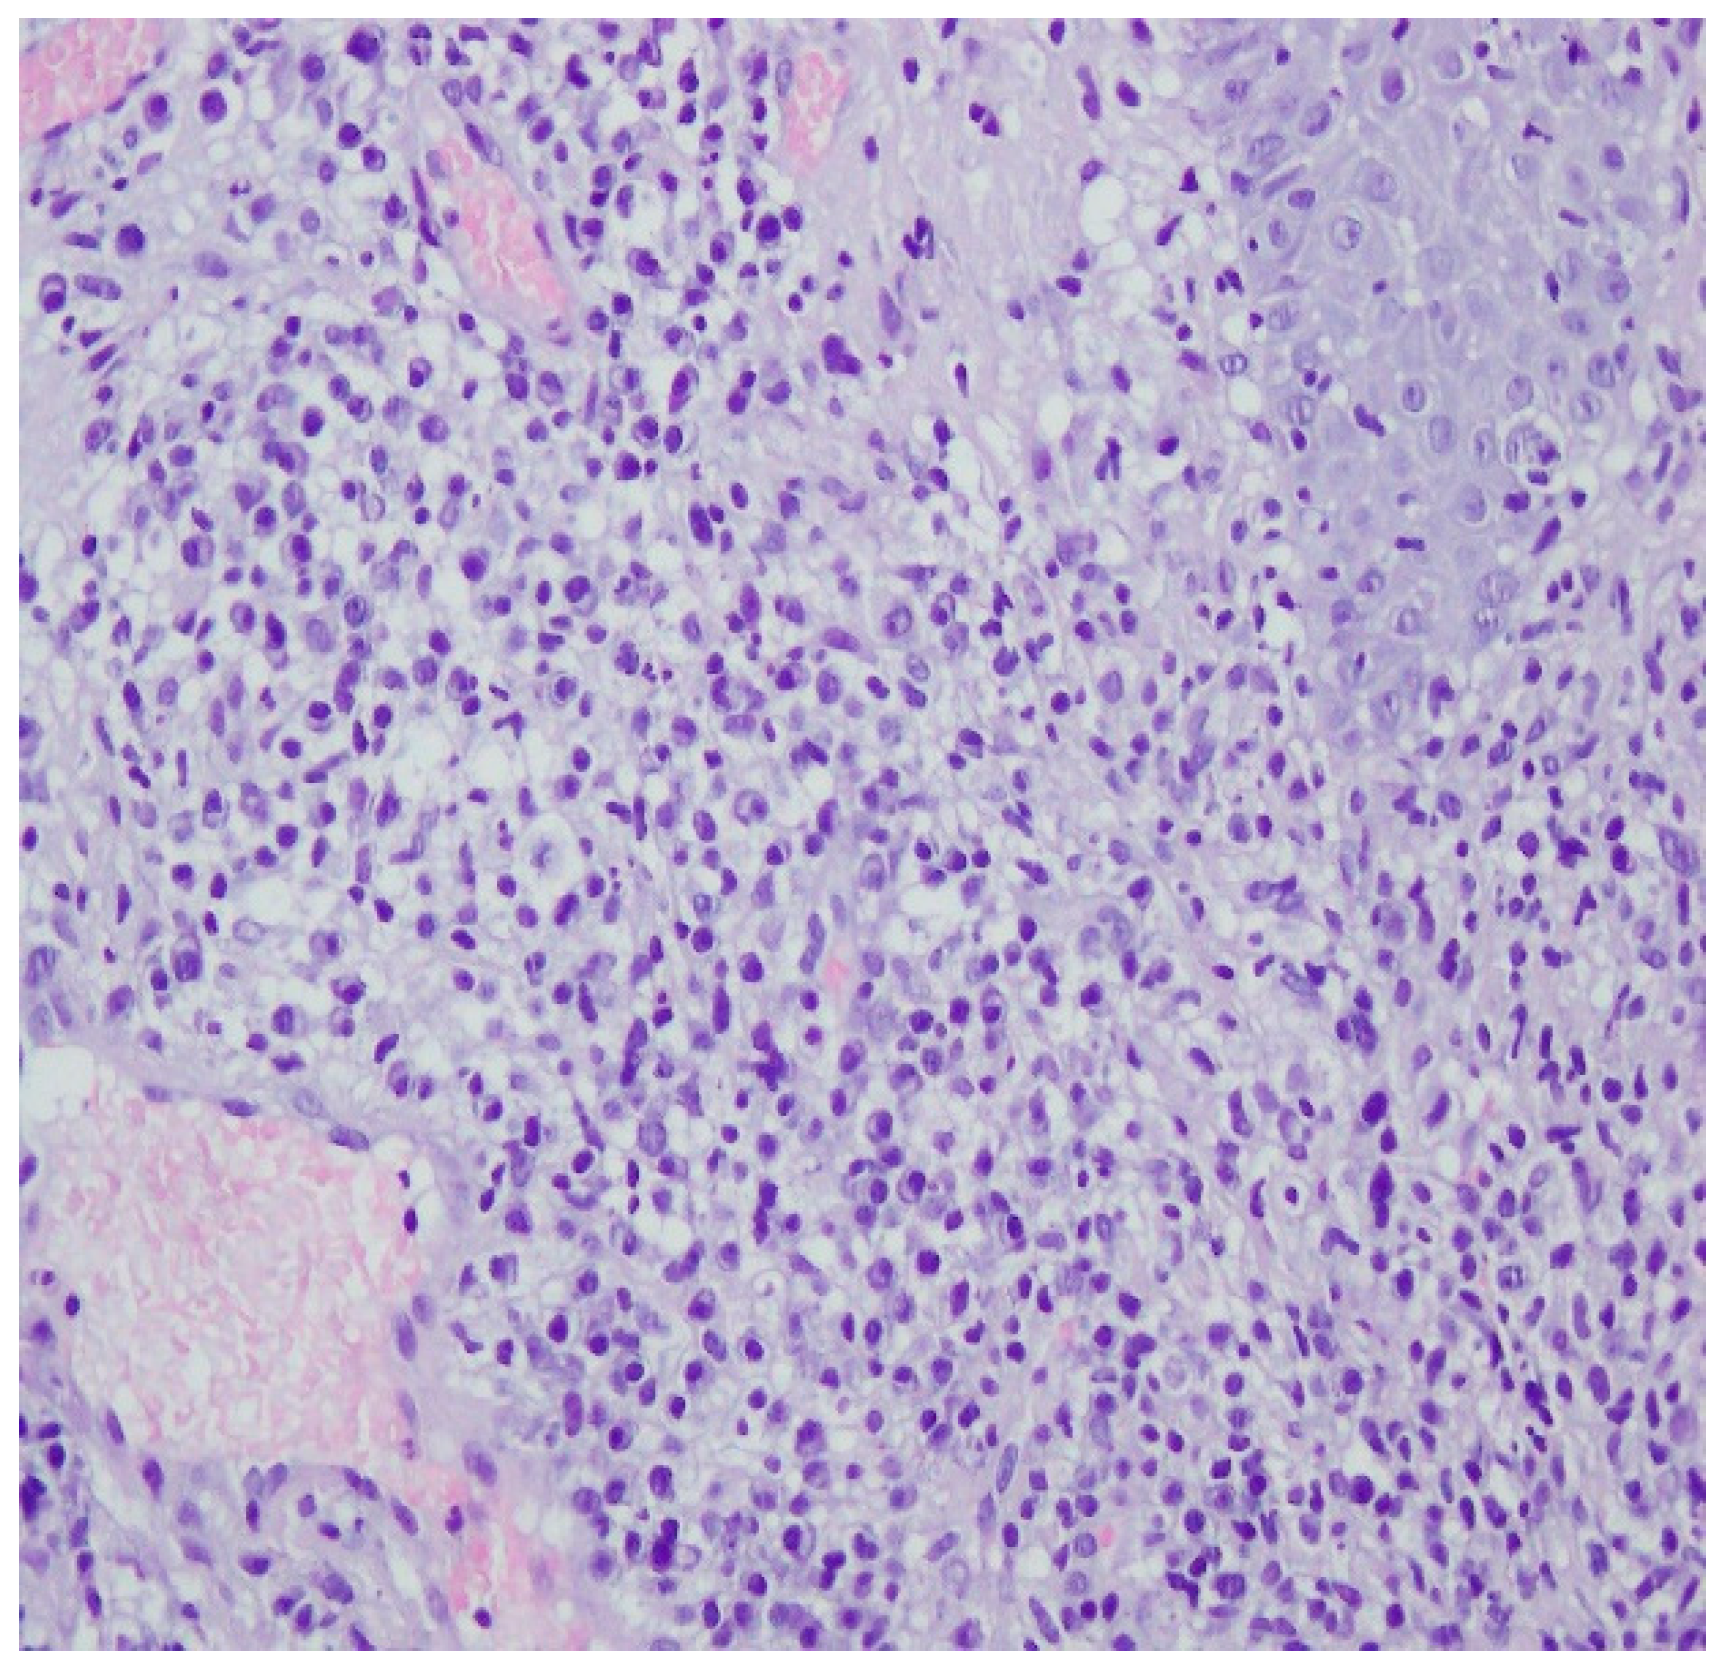

A histopathological examination of the skin lesion performed during hospitalisation revealed a thickened non-regular epidermis with streaky swelling, thinned by lymphocytic and histiocytic inflammatory infiltration with single plasmacytes. Slightly thicker infiltration presented in the area of enlarged vessels of the superficial plexus. There was a lack of characteristics typical for active pyoderma gangrenosum. This clinical picture can be consistent with secondary/tertiary syphilis (Figure 8 and Figure 9).

Figure 8.

Thickened non-regular epidermis with streaky swelling, thinned by lymphocytic and histiocytic inflammatory infiltration with single plasmacytes. Slightly thicker infiltration in the area of enlarged vessels of the superficial plexus. Lack of characteristics typical for active pyoderma gangrenosum. The clinical picture can be consistent with secondary/tertiary syphilis.

A revision of the biopsy from September 2021 showed a thickened epidermis and lymphocytic and histiocytic inflammatory infiltration with multiple plasmacytes (Figure 10 and Figure 11).

Figure 10.

Thickened epidermis. Lymphocytic and histiocytic inflammatory infiltration with multiple plasmacytes. Histopathological picture and data from the history are consistent with syphilis.